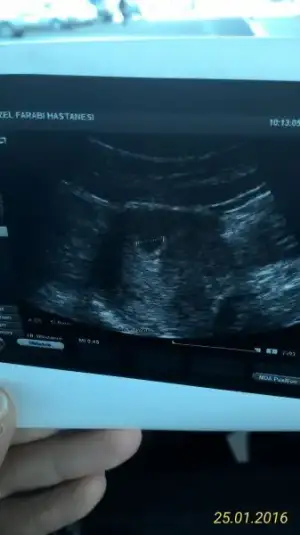

Canım yazıyor usg kağıdında, baktın mı, ben ekliyorum bak, beni 2-2,5 hafta sonra çağırdı özeldeki doktorum ama, ben perşembe günü diğer doktoruma da gideceğim.

• P_20160125_103750_1_p.webp

P_20160125_103750_1_p.webp

10,4 KB · Görüntüleme: 101

tesekkur ederim Bilmiyorum ki bende anlamadım canim tecrubemde yok yolk kesesi nedir onu dahi bilmiyordum böyle ultrasyon fotolarina baktım öyle gördüm sonra benim ultrasyona baktım dedim acaba dedikleri bu BeyaZlık olabilir mi dedim bir umut girdi içime,doktor dedi kese 30 mm ama boş içinde bebek yok dedi bu buyuklukteki kese de görünmesi gerekirdi ve 7+5 günlük dedi geç dollenmedir inşallah canım